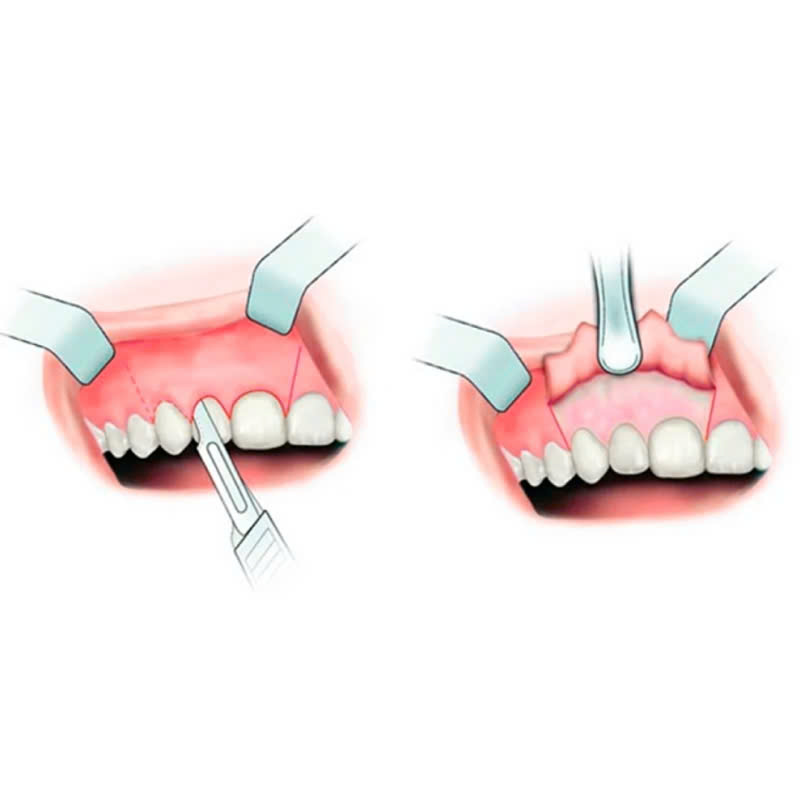

- Phẫu thuật

Bác sĩ sẽ thực hiện phẫu thuật theo phác đồ đã được lên kế hoạch, sử dụng dụng cụ chuyên dụng để điều chỉnh kích thước và hình dạng của xương ổ răng.